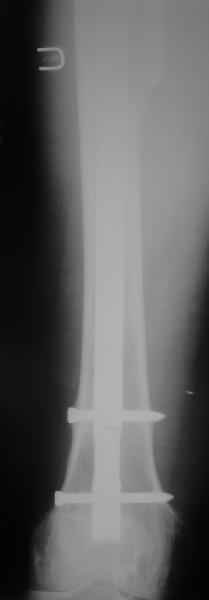

Произведено закрытое удлинение ножки эндопротеза с помощью ретроградного интрамедуллярного стержня. Продолжительность операции 3 часа. Два из них закрытое восстановление длины бедра диистрактором

таз-бедро.

новые снимки

Пациента удалось осмотреть недавно. Достигнутый результат сохраняется. Перелом бедра сросся. Конечность опорная и безболезненная, ходит без трости. Ножка, похоже, реинтегрировалась, как и надеялись. Снимки и фото в приложении. Комментарии приветствуются.

Надо ли что-то делать дальше, как полагаете? Убрать винты? Убрать "удлинитель ножки"? Или оставить все, как есть? Спасибо заранее.